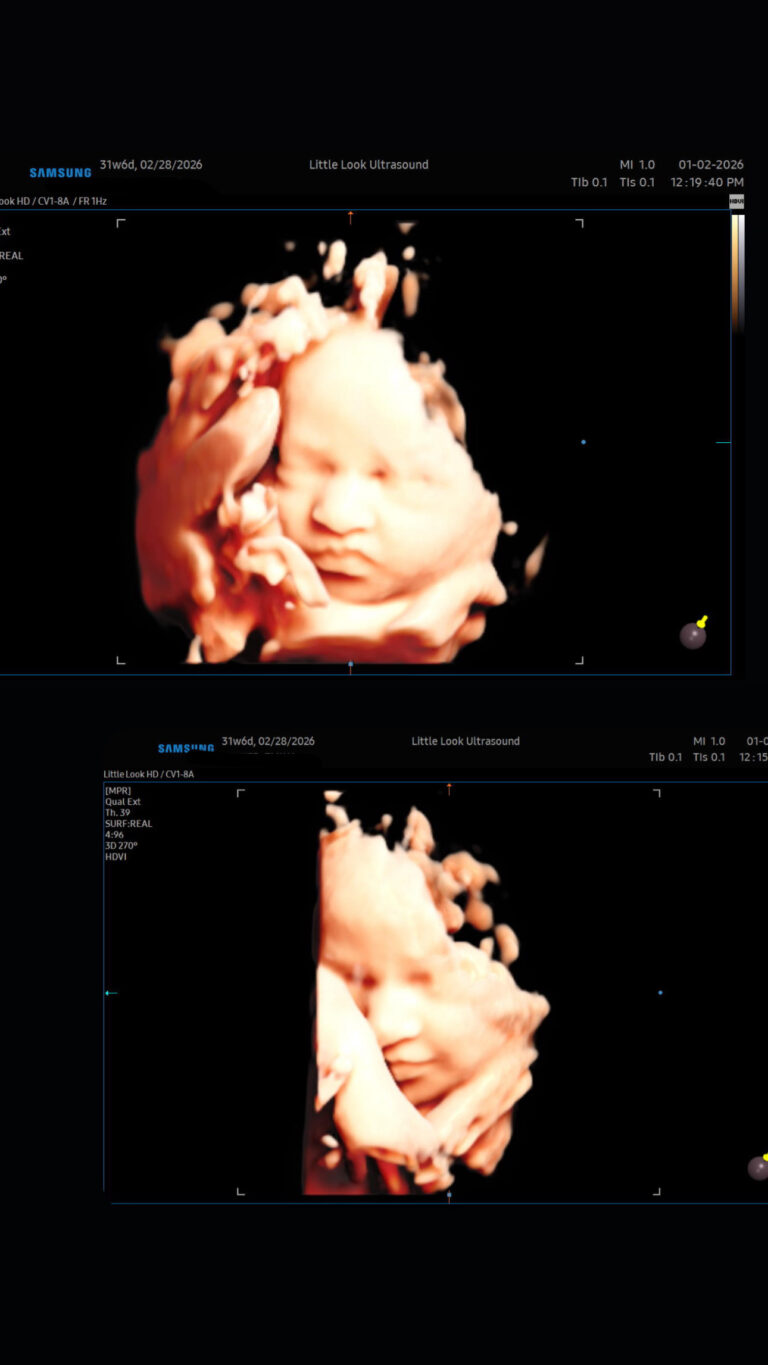

• 3d 4d private ultrasound sonogram third trimester baby scan imaging

3D 4D Ultrasounds

Why book a 3D 4D Baby Ultrasound?

Byadmin January 4, 2026January 4, 2026

Book your 3D 4D baby imaging with Little Look Ultrasound in Southern NH near MA, Located in Londonderry

• 3d baby scan in New Hampshire elective ultrasound studio boutique, 4d ultrasound technology and video in southern New Hampshire near massachusetts

NH Elective ultrasounds in new hampshire near massachusetts

Byadmin September 3, 2025September 3, 2025

See Your Baby Sooner: Elective Ultrasound in NH and MA Pregnancy is a journey filled with excitement, love, and anticipation. While medical ultrasounds play an important role in monitoring your baby’s health, many parents are choosing elective ultrasound in NH and MA for the chance to bond with their little one in a fun, relaxed environment. What…

Little Look Ultrasound proudly offers elective 3D/4D HD keepsake ultrasound services in Londonderry, New Hampshire, offering expectant families across Southern NH and Massachusetts including the Greater Manchester area and Boston MA areas a magical first glimpse into their baby’s world. Our advanced imaging technology captures every smile, stretch, and tiny yawn in stunning detail, creating beautiful keepsake photos and videos you’ll cherish forever. Whether it’s your very first peek or a special milestone session, each ultrasound is designed around your needs—with a cozy studio, relaxing atmosphere, and customizable photo and video packages.